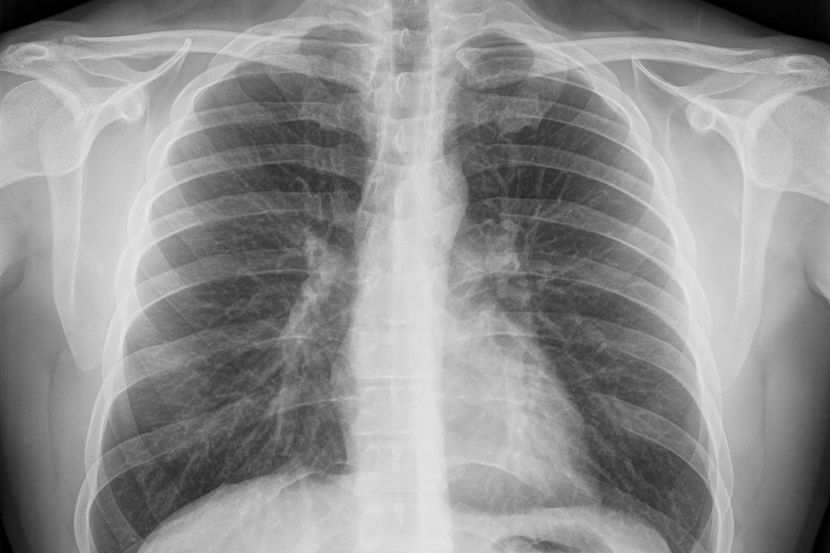

Teška infekcija pluća tokom kovida-19 može oštetiti srce

Studija se fokusirala na oštećenje srca ljudi sa akutnom respiratornom insuficijencijom (ARDS) povezanom sa SARS-CoV-2, ozbiljnim oboljenjem pluća koje može biti smrtonosno. Međutim, istraživači kažu da bi nalazi mogli biti relevantni i za druge organa i viruse, piše MedicalXpress.